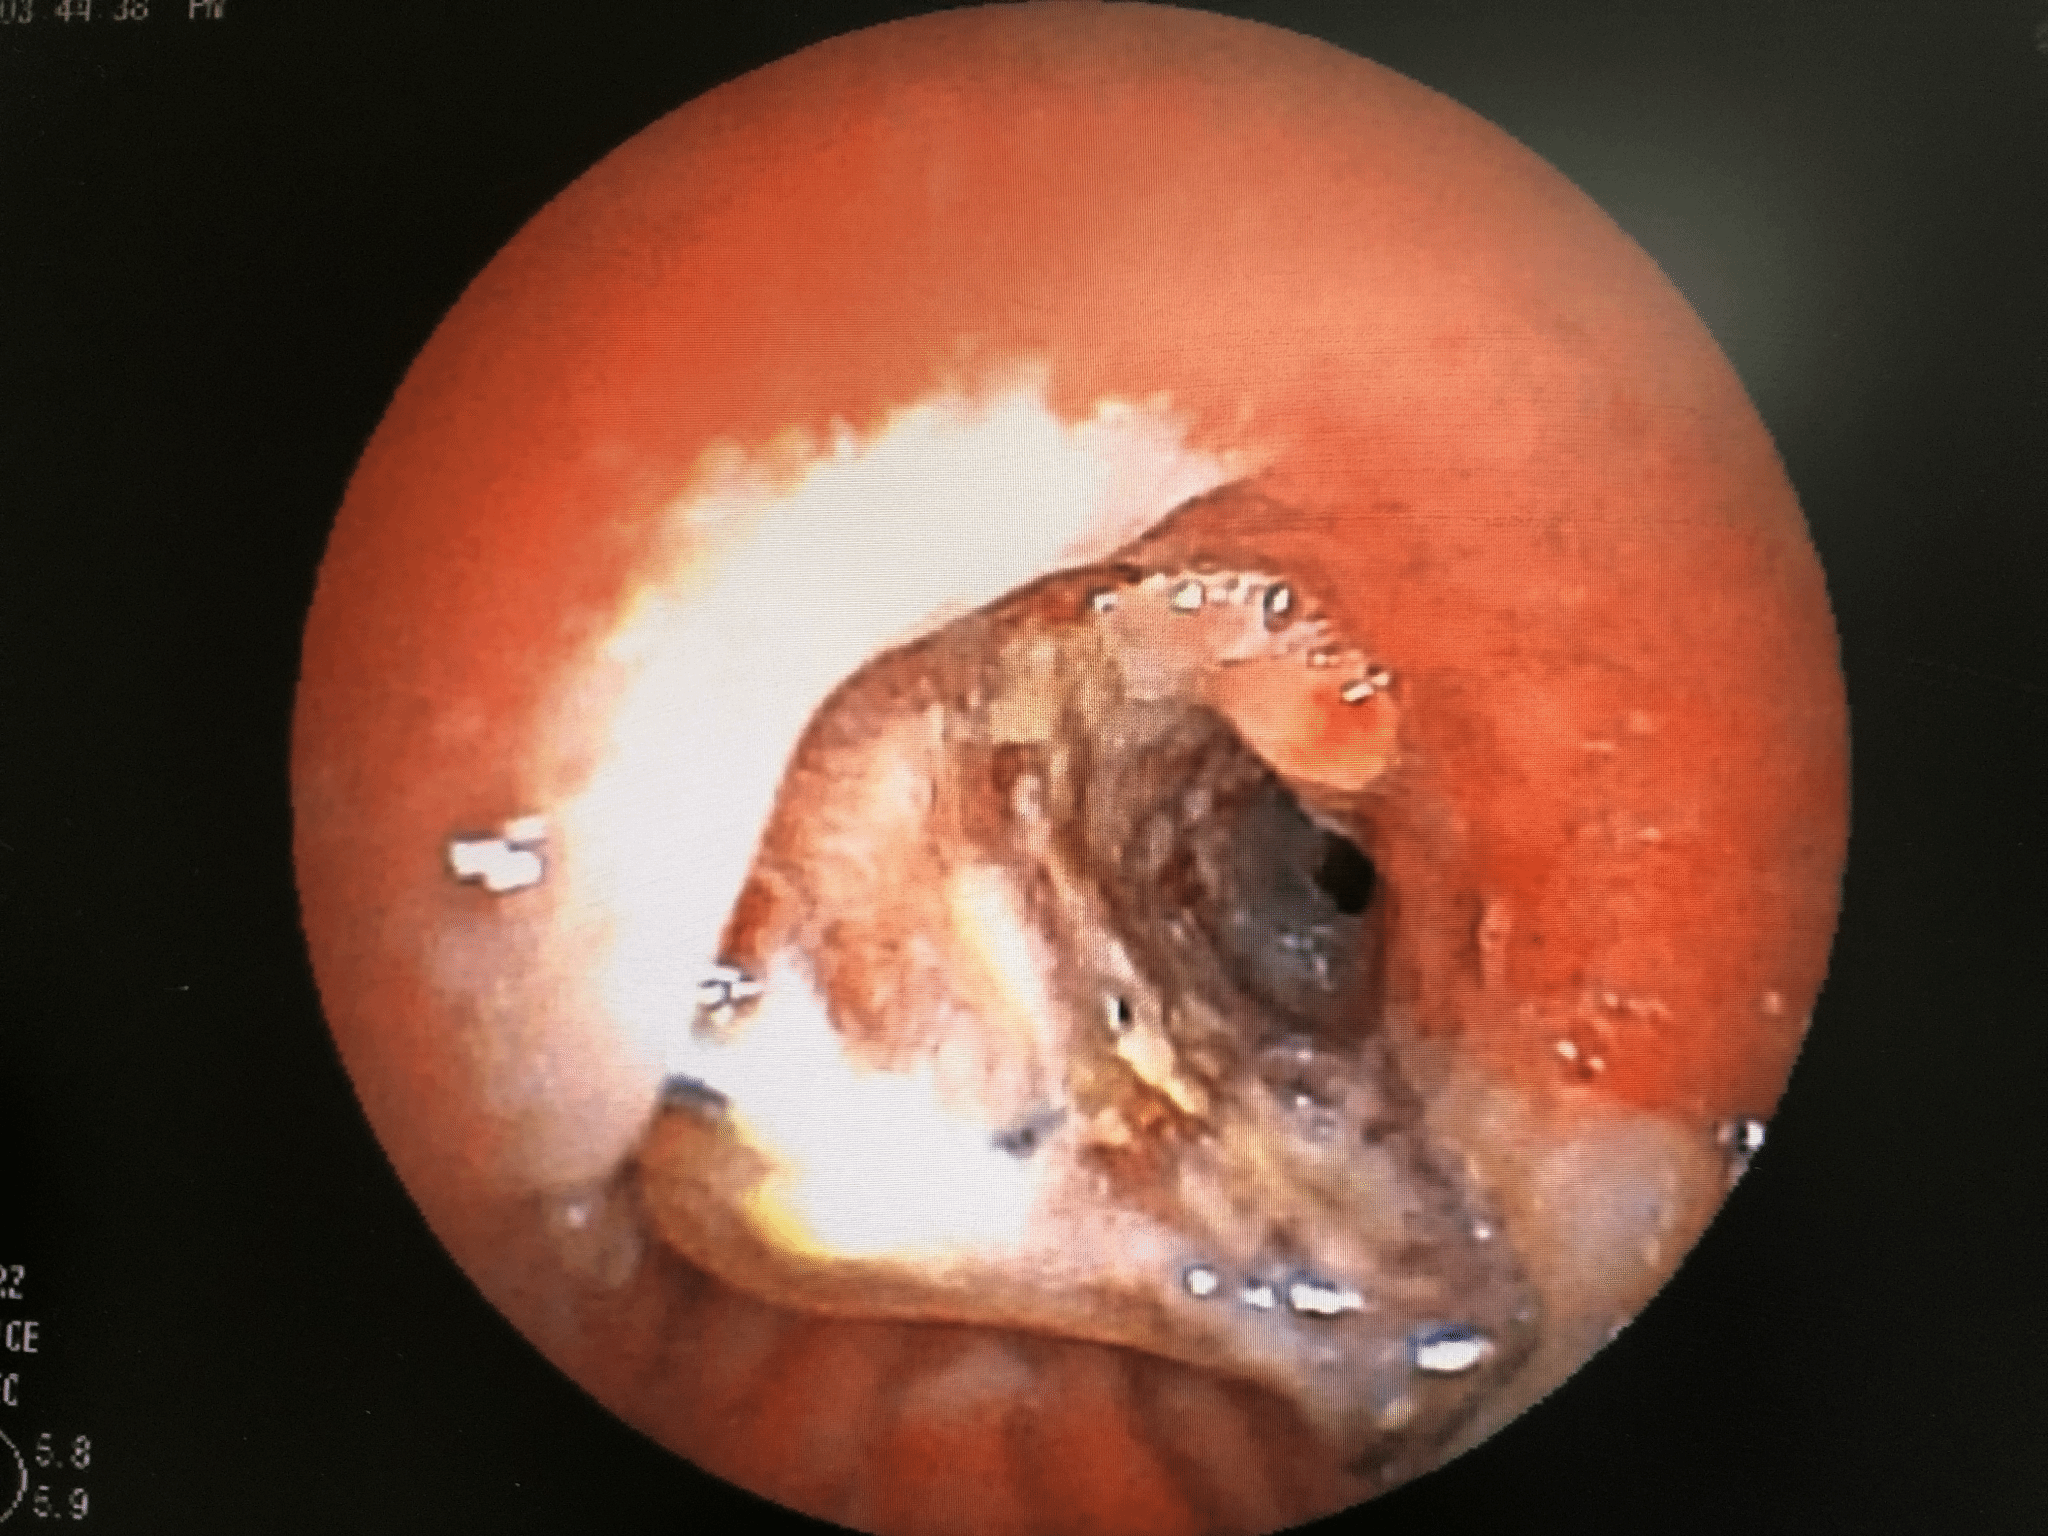

冷冻治疗术

冷冻治疗前 冷冻治疗中

冷冻治疗后 冷冻取出新生物